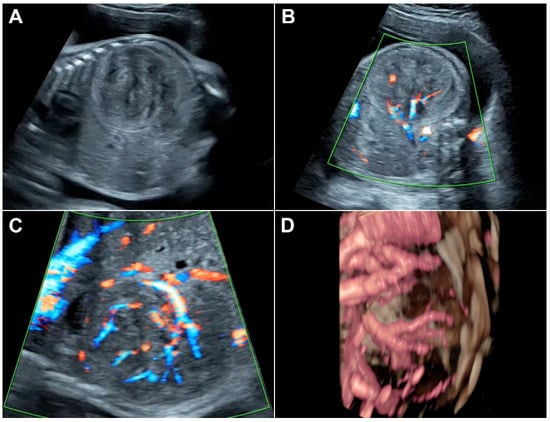

3. Index Case with Typical Images as an Educational Tool

| Index case | 23 | 1 | 30 | 4.8 | Yes | No | Left | Heterogeneous | Solid | Well | Strong | CS | Male | 31 | 1685 | 8 | 10 | Survive | 730 | Nephrectomy |